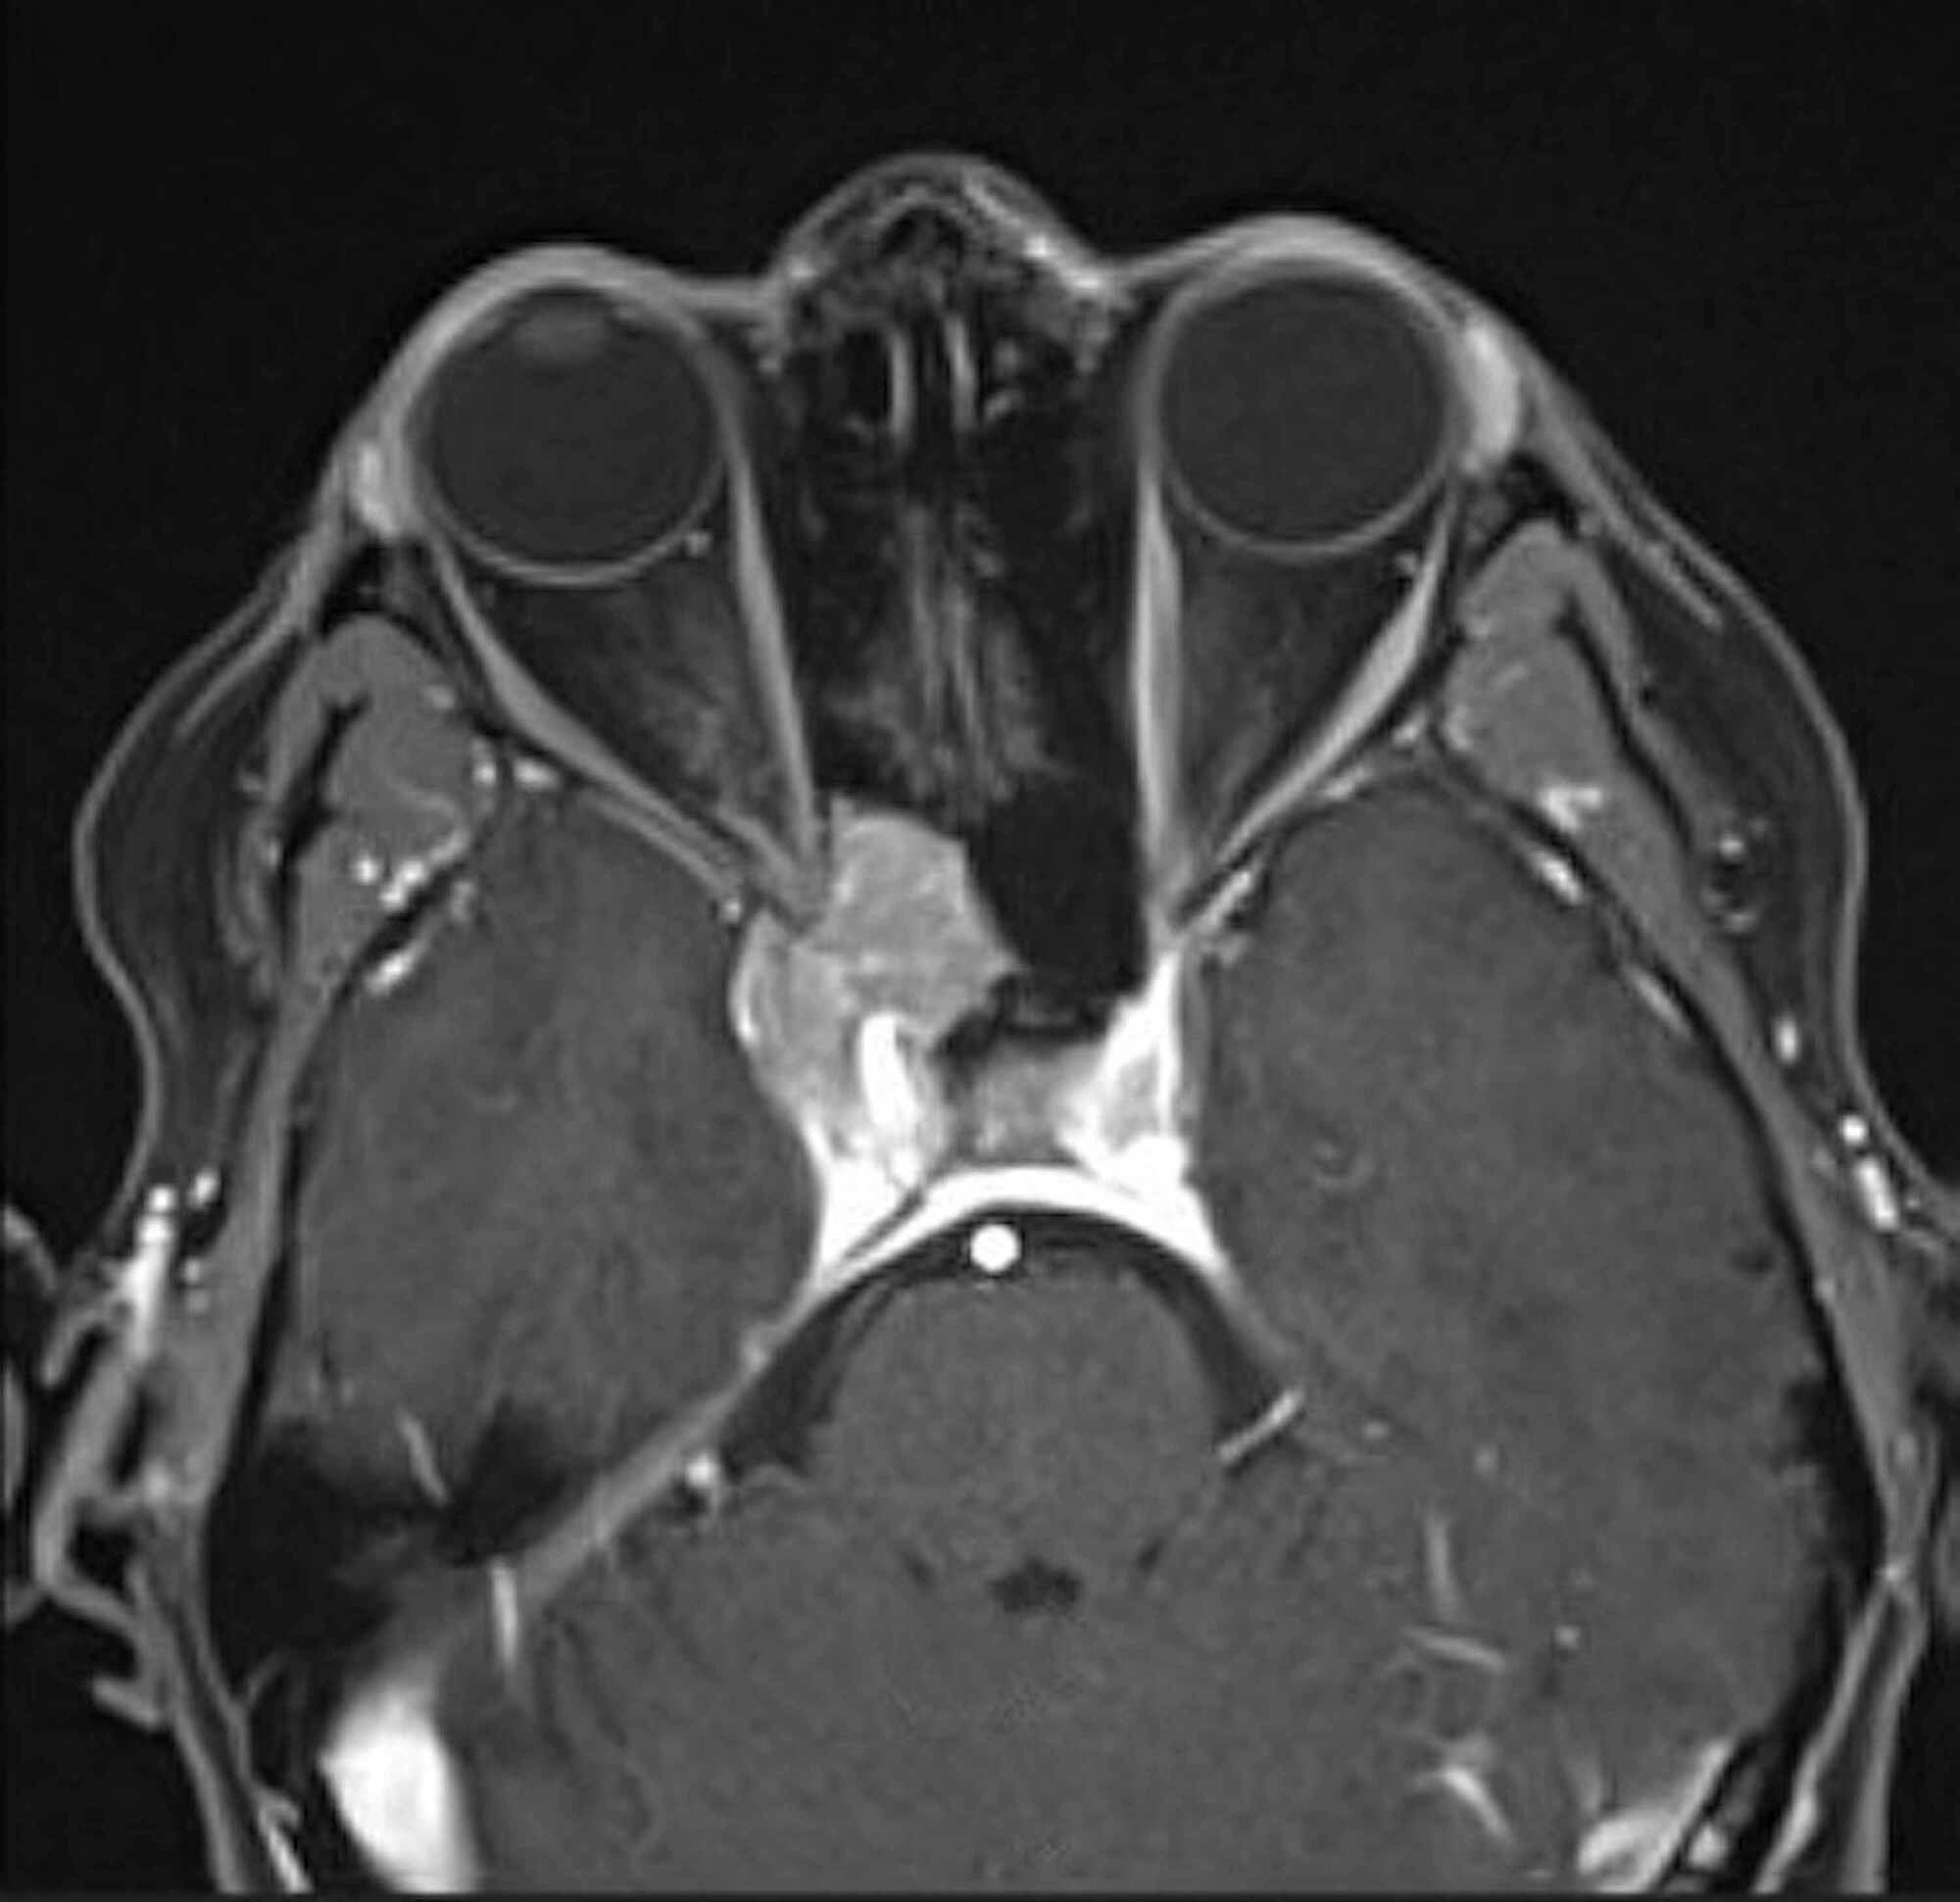

MRI scan of cavernous sinus mass. Coronal postgadolium enhanced T1 MRI Mri Anatomy Cavernous Sinus The cavernous sinus is a paired, venous structure located on each side of the sella turcica, a bony depression in the skull base. The purpose of this article was to review the. The cavernous sinus (cs), which is a critical region in the skull base, contains a complex mixture of the cranial. The main purpose of this pictorial review is. Mri Anatomy Cavernous Sinus.